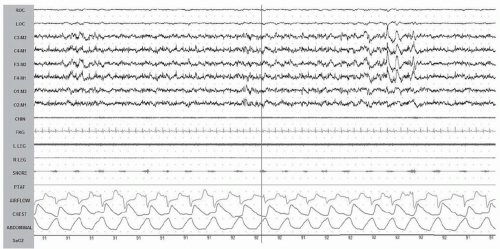

When scoring respiratory events, it is important to record the proper signals using the appropriate sensors (1). We should be recording airflow using an oronasal thermal sensor (this includes thermistors, thermocouples, or polyvinylidene fluoride airflow sensors) or a nasal pressure transducer. For respiratory effort channels, thoracic and abdominal respiratory inductance plethysmography (RIP) belts are recommended. The RIPsum and RIPflow channels can be a helpful tool for scoring respiratory events. See Figure 39-1 for an example of a normal respiratory pattern.

![]() Figure 39-3 A, B: Central apnea. In this example, the airflow as well as the respiratory effort is completely absent. PTAF, pressure transducer airflow. |